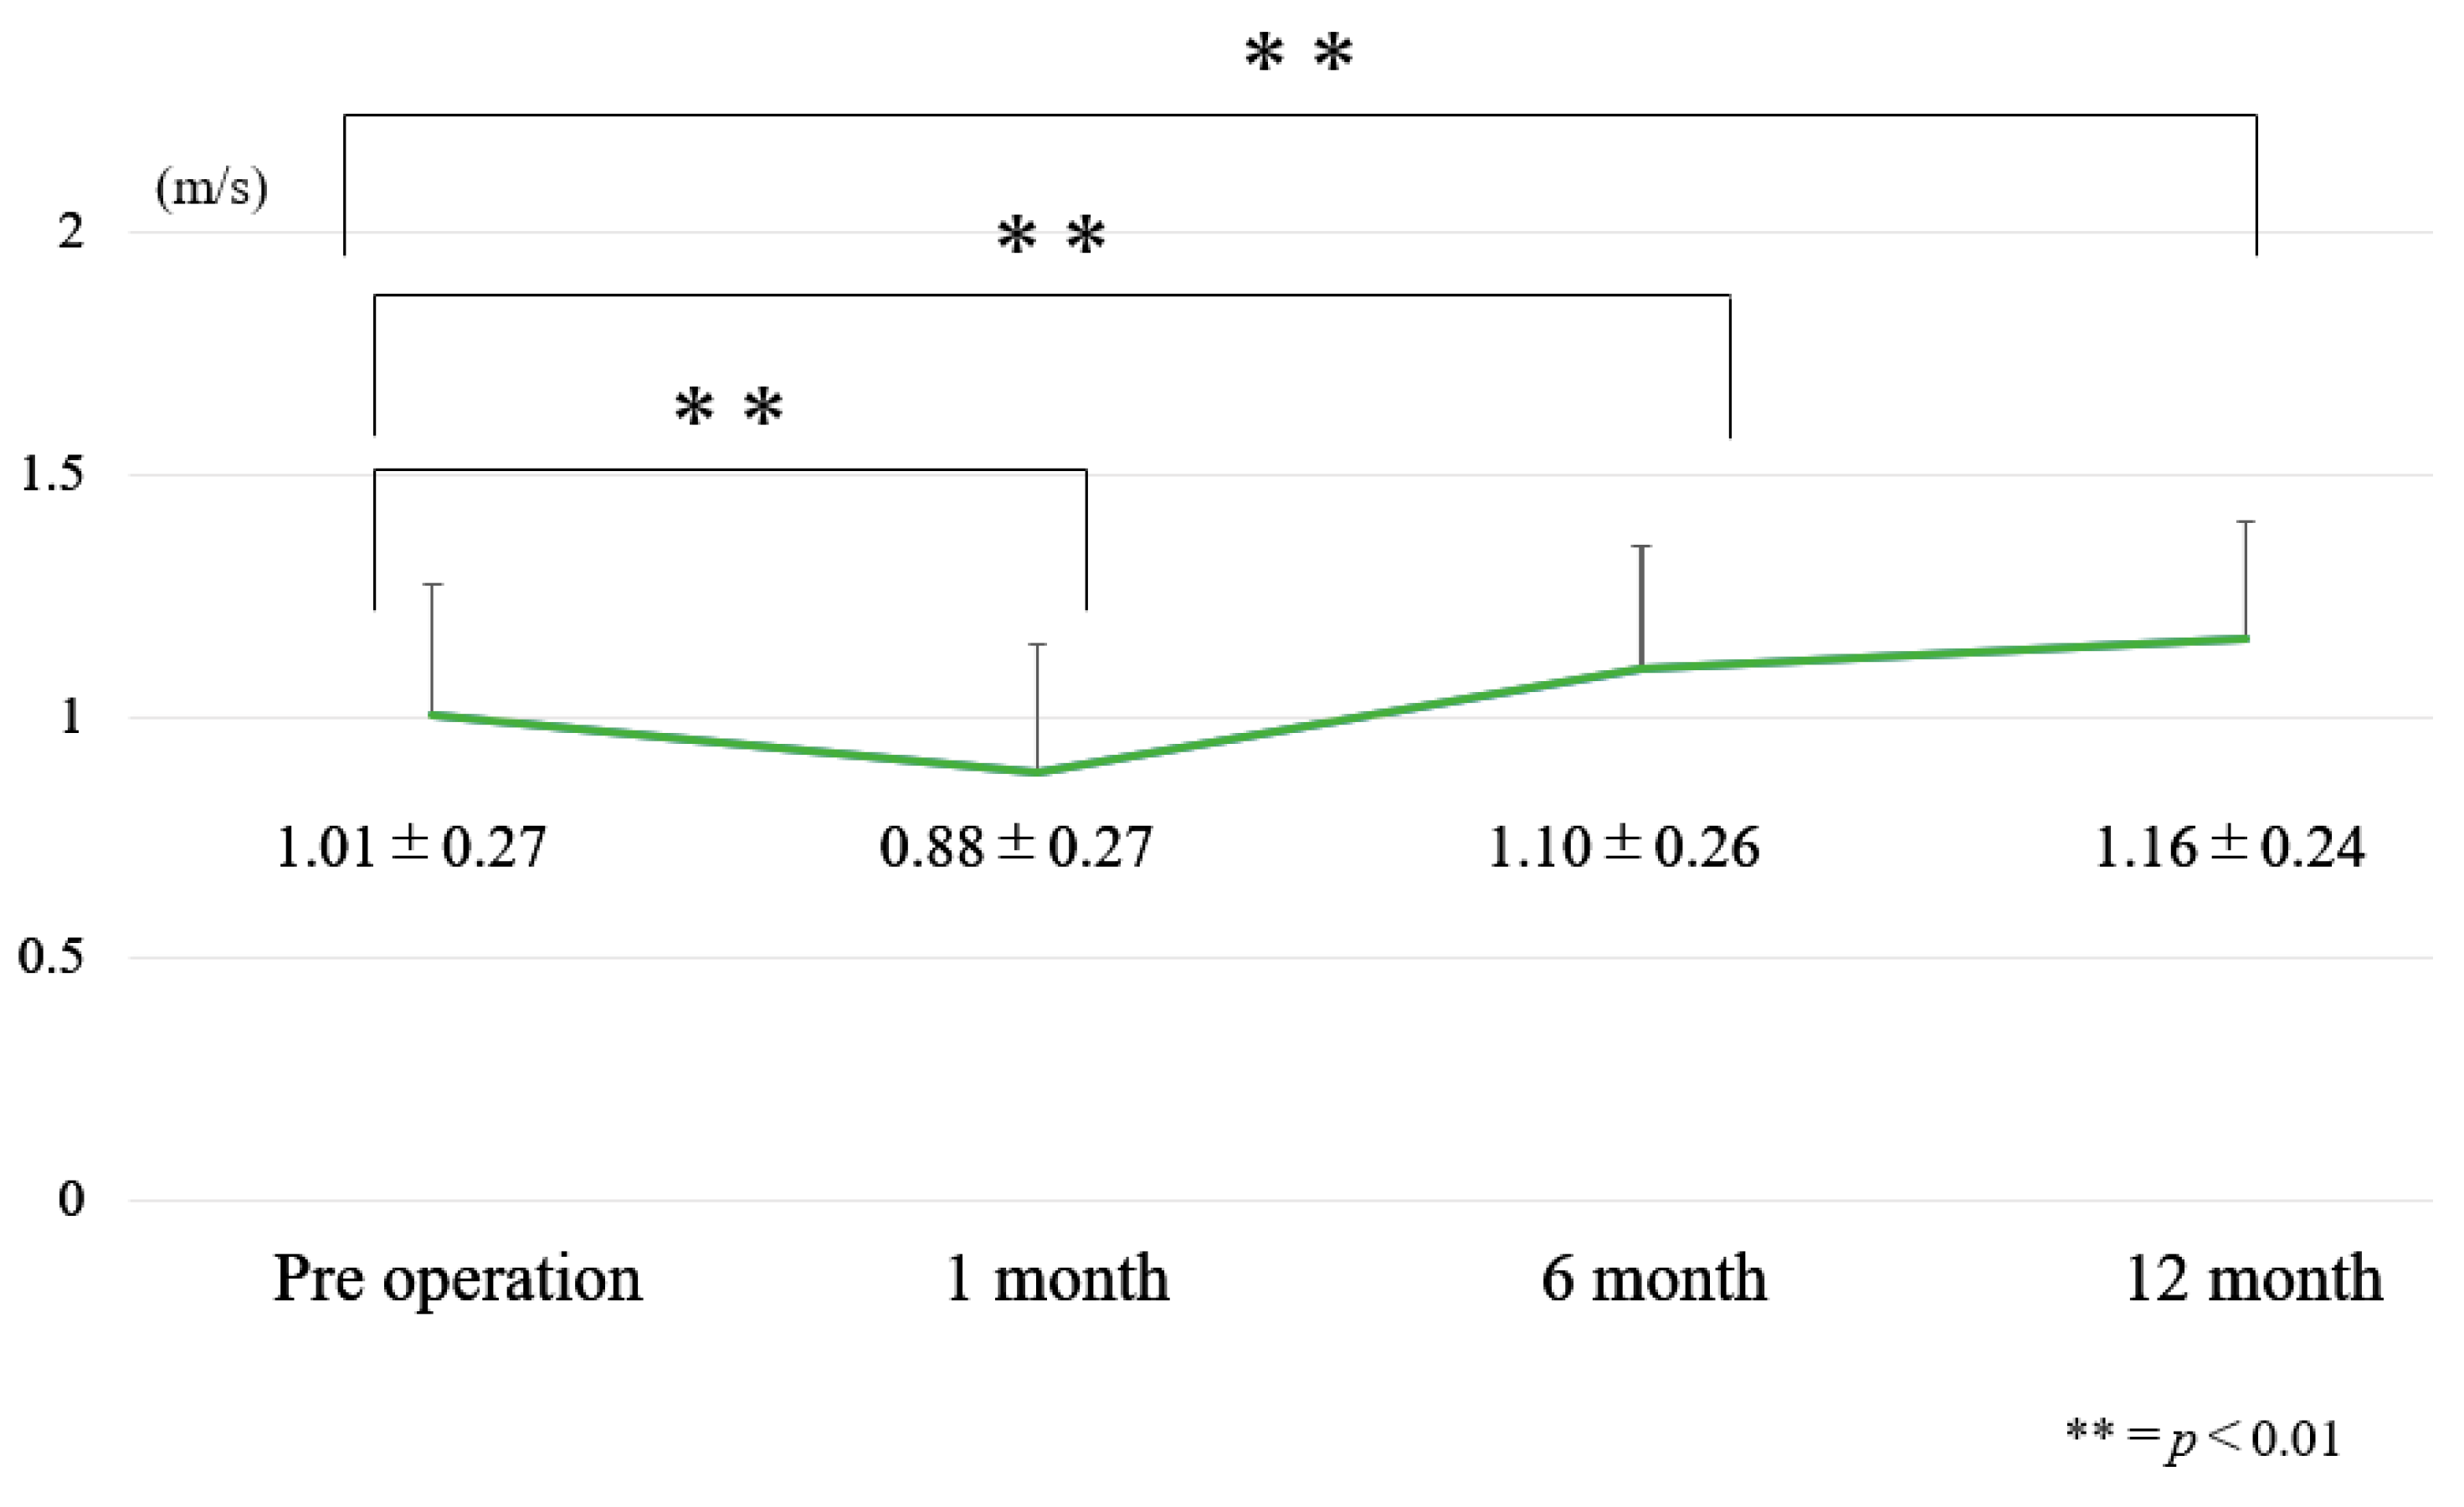

2.2.1. Ten Meter Walk Velocity

3.1. Chronological Results of 10 m Walk Velocity and TUG (Figure 6 and Figure 7)

3.2. Internal Responsiveness